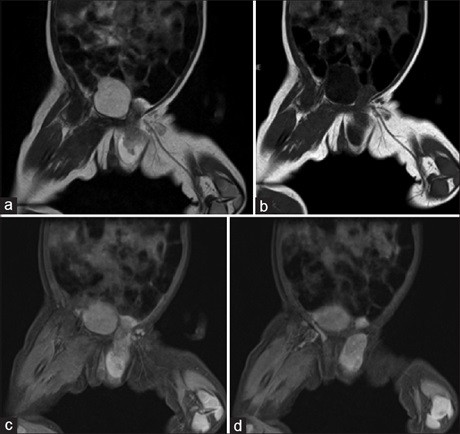

Hydrocele of the canal of Nuck is a rare cause of inguinal swelling in females. It is usually seen in the newborn and in children and rarely seen in adult females. We report a case of hydrocele of the canal of Nuck in an 18‑month‑old female who presented with a swelling in the left inguinal region, extending into the labia majora. Abdomino‑pelvic ultrasonography revealed a tortuous heterogeneously hyperechoic structure inside an anechoc sac. Magnetic resonance imaging was done for further evaluation, which showed an elongated cystic lesion in the left inguinal region extending into the left labia majora. There was a heterogeneous tubular structure seen inside the sac, which appearance resembled the round ligament and ovary. These findings were suggestive of hydrocele of the canal of nuck with herniation. Surgery was done which confirmed a hydrocele of the canal of Nuck with herniation of the round ligament, left ovary and part of the uterus in the sac.